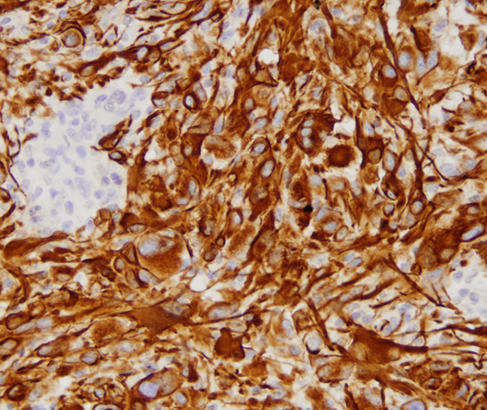

reactive brain with foamy macrophages

Brain met

cytokeratin stain

Stain for brain met

Cytokeratin